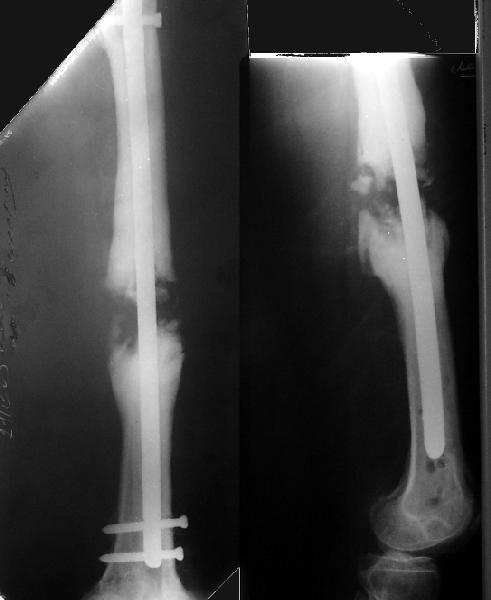

Возможно, проф. Лазарев предложит другой вариант, а в наших условиях мы бы закрыто заштифтовали бы бедро антеградно. Устранили бы варус, используя голень как рычаг, вероятнее всего, даже дистрактор не понадобился бы. В приницпе, можно и ретроградно ири наличии движений в колене, но варус будет труднее устранить - можно и предварительно аппаратом в таком случае.

Стержень можно использовать и обычный потолще, но лучше бы с возможностью введения большего, чем два фронтальных, числа запирающих винтов.

Учитывая наличие этой мощной спайки, запереть можно сразу динамически.

Рефрактур уж точно можно будет не опасаться, а за несколько месяцев даже при отсутствии заполнения костью по всей окружности, этот обходной "мостик" упрочнится и возьмет на себя нагрузку. В приложении пример такого рода "эндопротезирования диафиза", прошло больше 3 лет.

Пациентка, страдающая еще и инсулинозависимым диабетом, не хромает, работает инженером.